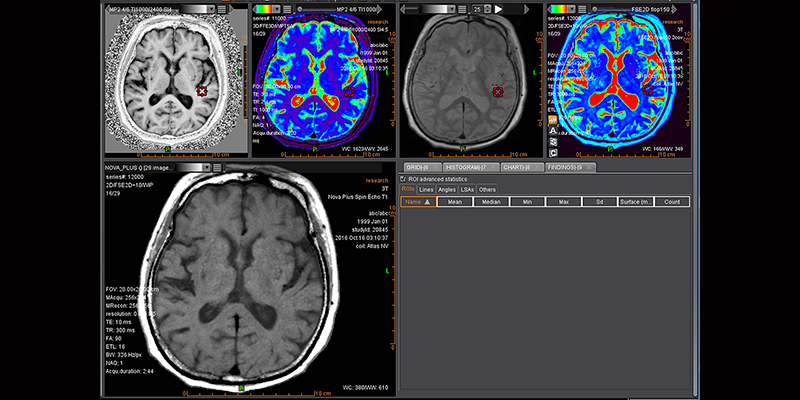

Додаток MR Neuro

Додаток Neuro інтегрований у розширену візуалізацію Vitrea і забезпечує спеціальні протоколи для пухлини мозку та розширені протоколи інсульту, які забезпечують швидку оцінку захворювань головного мозку.

Обчислює оптимізовані параметричні карти (rBV, rBF, TTP, MTT, TMAX, tMIP) із первинної перфузійної серії

Використовує автоматизований та настроюваний робочий процес

Включає повністю автоматизовану поетапну обробку для пацієнтів з пухлинами мозку, включаючи кількісний та якісний мультипараметричний аналіз

Забезпечує корекцію витоку контрасту та створення карти K2 rBV

Пропонує один спеицифічний додаток: Розширений додаток Brain Tumor DSC DCE Expanded